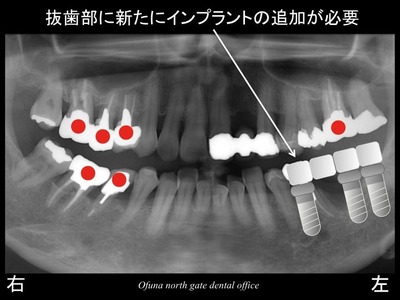

以下の赤丸()が神経がない歯です。

スライド11

欠損部手前の歯は、

神経がないこと、

歯が斜めになっていること

を考えると将来的に歯根破折 を起こしてもおかしくない歯です。

もし、欠損部手前の歯を抜歯しないで 奥にインプラント治療を行った後で

手前の天然歯がダメになった場合には

新たに追加のインプラント治療が必要になります。